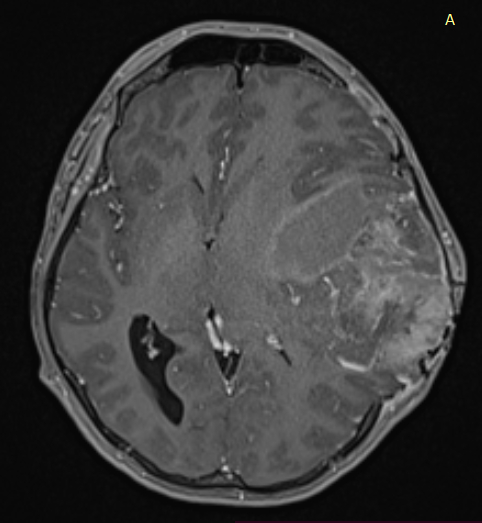

Temporal ependymomas are exceedingly rare intracranial neoplasms originating from ependymal cells within the temporal lobe. The rare nature of these tumours makes diagnosis and treatment extremely difficult in the field of neuro-oncology. These tumours frequently encounter misdiagnosis as meningiomas or other extra-axial lesions due to their atypical location and the absence of distinctive features. Consequently, histopathological examination becomes essential for accurate evaluation and a precise diagnosis. This article presented a unique case of a 25-year-old male patient’s supratentorial ependymoma at the temporal region. The report described the patient’s clinical presentation, including progressive headaches, abnormal behaviour and vomiting, leading to timely diagnostic investigations. After a surgical resection, the diagnosis of ependymoma was confirmed by histopathological analysis. Following surgery, the patient defaulted follow-up and presented six months later with worsening symptoms. Radiological imaging proved the tumour’s significant growth. The second resection worsened his neurological deficits. Unfortunately, adjuvant radiotherapy would not be beneficial to him at this point. He received palliative care. The case study emphasises the difficulty in diagnosing and treating temporal ependymomas, underscoring the importance of multidisciplinary collaboration and evidence-based approaches for optimal patient outcomes.